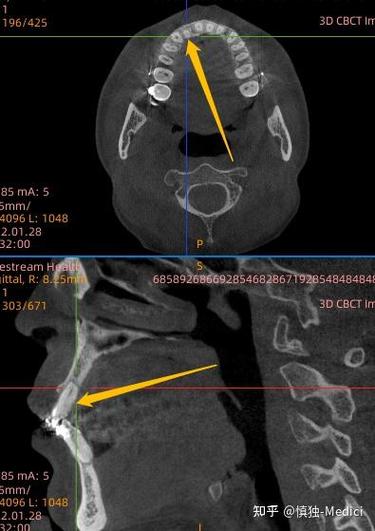

以深圳北大口腔某患者案例为例:25岁女性患者因牙齿拥挤选择该机构进行正畸,医生设计拔除四颗前磨牙的方案,治疗过程中患者多次反馈“咬合不适”,但医生解释为“正常调整期”,拆除矫治器后,患者发现牙齿中线偏移0.5cm,后牙咬合过紧,且出现颞下颌关节弹响疼痛,后续影像学检查显示,部分牙根吸收达1/3,牙槽骨厚度减少,与机构沟通时,对方称“个体差异”拒绝赔偿,患者不得不通过法律途径维权,耗时近两年才获得部分赔偿。

| 牙周组织损伤 | 牙龈萎缩、牙槽骨吸收、牙齿松动 | 口腔卫生差、正畸力过大、未治疗牙周炎 |

| 牙根吸收 | 牙根长度缩短、牙齿敏感 | 力度过大、治疗时间过长、个体易感性 |